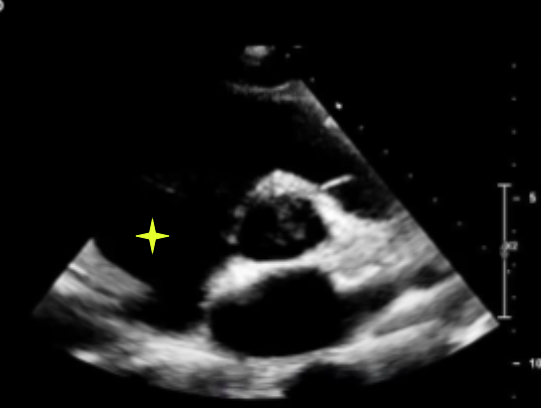

grade 1